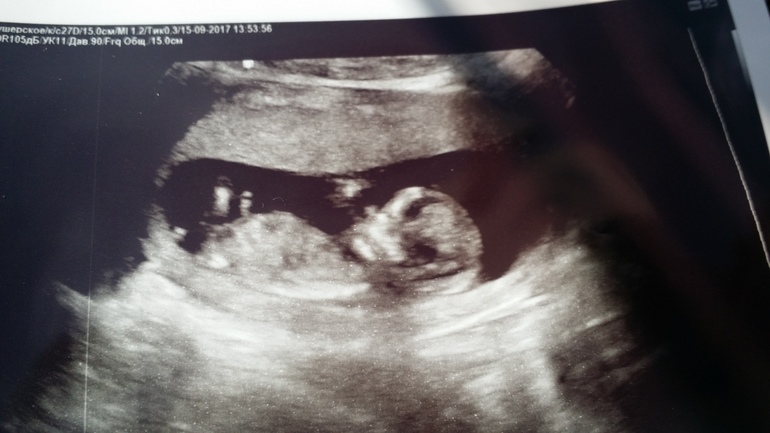

УЗИ 1 скрининг

Вот и первое "официальное" УЗИ позади. Ляля 66мм, чуть больше срока по размерам, стопушка почти 1 см в длину))) Врач очень долго смотрел, очень устала, конечно, очень волнительно, когда долго смотрят,практически молча, периодически отправляя сначала попить воды, потом сходить в туалет, потом повернуться на левый бок, потом опять на спину 😱и так я ходила в туалет раза 4 )) но в итоге все хорошо. Дали 80% вероятности, что у нас Ксюха, я-то не сомневаюсь, а вот мужчины мои,как мне показалось, надеятся на оставшиеся 20%😏

Ну и Ляля наша

посмотрела фото УЗИ и почему-то сразу показалось, что девочка! Такая нежная, милая, с аккуратненьким носиком 😃